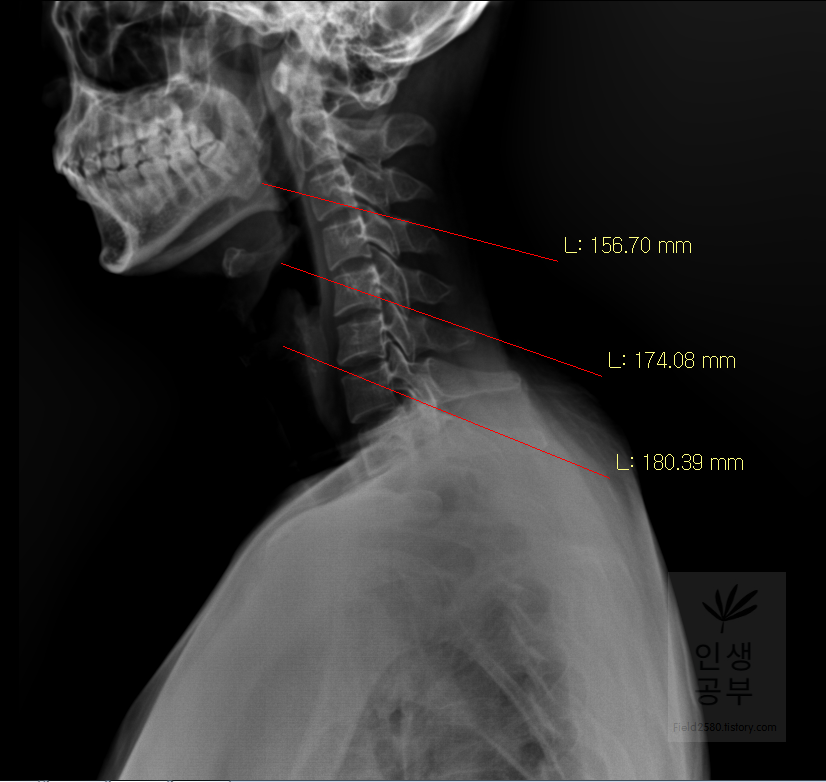

일곱번째 목뼈 추체 밑면(Inferior endplate of C7)과 평행한 선을 그어줍니다.

위쪽에 있는 선은 첫 번째 목뼈(C1) 선을 그리기 위해 제일 튀어나온 앞쪽 부분 가운데 지점에(Center of Anterior arch)에서 시작해서 후궁(Posterior arch) 제일 좁은 부위 가운데를 지나는 선이 되도록 이동해줍니다. 선 이름을 고리 뼈 선(APL : Atlas Plane Line)이라고 합니다. 점은 조금 더 정확하기 위해서 하는 것이 찍어도 되고, 점을 찍지 않은 상태에서 선을 그으셔도 무방합니다. 아래쪽에 있는 선은 일곱번째 목뼈 추체 밑면(Inferior endplate of C7)과 평행하게 선을 맞춰줍니다. 노란색 글자와 숫자가 아래줄 맞춰 준 곳에 있는데 A는 Angle 각도이고 옆에 있는 숫자가 Cobb 각입니다.

목의 정렬을 알아보기 위해서 목뼈의 선들을 연결해서 그어보는 방법에 대해서 알아보겠습니다. 도구 상자에서 빨간색네모상자 안에 있는 물결무늬 모양의 버튼을 눌러줍니다.

목뼈 추체 제일 앞쪽에 있는 선을 따라서 그어줍니다.

목뼈 추체 뒷면을 따라서 선을 그어줍니다.

Spinolaminal line을 따라서 선을 그어줍니다.

극돌기(Spinous process) 끝을 따라 선을 그어줍니다. 각각의 라인의 곡선의 커브가 자연스럽게 연결되었는지 확인해 줍니다. 이처럼 연결된 선을 이용해서 각각의 뼈의 정렬을 선을 그어서 알아보고 싶으면 곡선으로 그려진 버튼을 이용해서 확인할 수 있습니다.